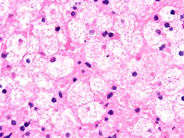

The company estimates that one in 10,000 live births will have npc. The company estimates that one in 10,000 live births will have npc. For people with mild to moderate type c, a drug called miglustat (zavesca) may be an option. These types are classified on the basis of genetic cause and the signs and symptoms of the condition. It belongs to a family known as lysosomal storage diseases and is caused by mutations leading to defective npc protein. This leads to the abnormal accumulation of these substances within various tissues of the body, including brain tissue. Type a, type b, type c1, and type c2. These cells malfunction and, over time, die.

The company estimates that one in 10,000 live births will have npc. Consult a doctor for medical advice. Type a, type b, type c1, and type c2. This leads to the abnormal accumulation of these substances within various tissues of the body, including brain tissue. These types are classified on the basis of genetic cause and the signs and symptoms of the condition. These cells malfunction and, over time, die. These cells malfunction and, over time, die. It is not a medical authority nor does it claim to have medical knowledge. The company estimates that one in 10,000 live births will have npc. For people with mild to moderate type c, a drug called miglustat (zavesca) may be an option. It belongs to a family known as lysosomal storage diseases and is caused by mutations leading to defective npc protein. Orphazyme a/s company announcement no. It has a wide range of symptoms that vary in severity.